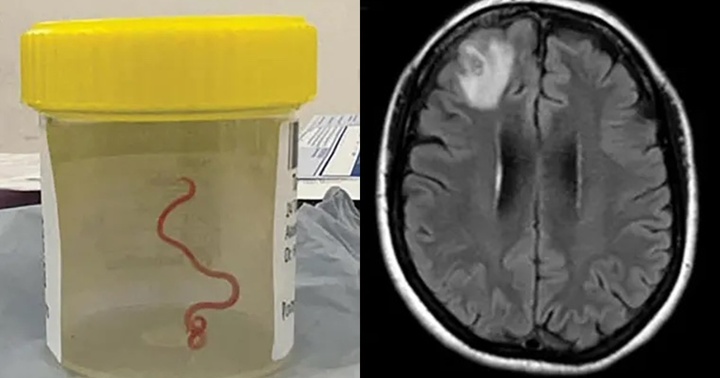

Sau khi khám và làm các xét nghiệm cận lâm sàng, kết quả cho thấy lượng bạch cầu ái toan trong máu 0,6 G/l (tăng so với bình thường), tỷ lệ bạch cầu ái toan trong dịch rửa phế quản 6% (tăng so với bình thường); xét nghiệm yếu tố viêm CRP tăng cao108,57; dương tính với giun đũa chó mèo; kết quả CT ngực: hình ảnh tổn thương đám mờ thuần nhất thuỳ trên phổi trái và thuỳ dưới phổi phải.

Sau khi hội chẩn các Bác sĩ đã đưa ra chẩn đoán người bệnh mắc viêm phổi tăng bạch cầu ái toan. Đây là một bệnh hiếm gặp với tỷ lệ 9,1/ 100.000 người dân/năm. Bệnh viêm phổi tăng bạch cầu ái toan có nguyên nhân liên quan đến việc hút thuốc lá, nhiễm kí sinh trùng, nấm,virus, hoặc do dùng một số thuốc.

Sau 8 ngày điều trị người bệnh hoàn toàn hết các triệu chứng, chụp CT ngực đánh giá các tổn thương tại phổi đã biến mất, người bệnh được ra viện, được kê bổ xung đơn thuốc tẩy giun (người bệnh có kết quả xét nghiệm dương tính với giun đũa chó, mèo).